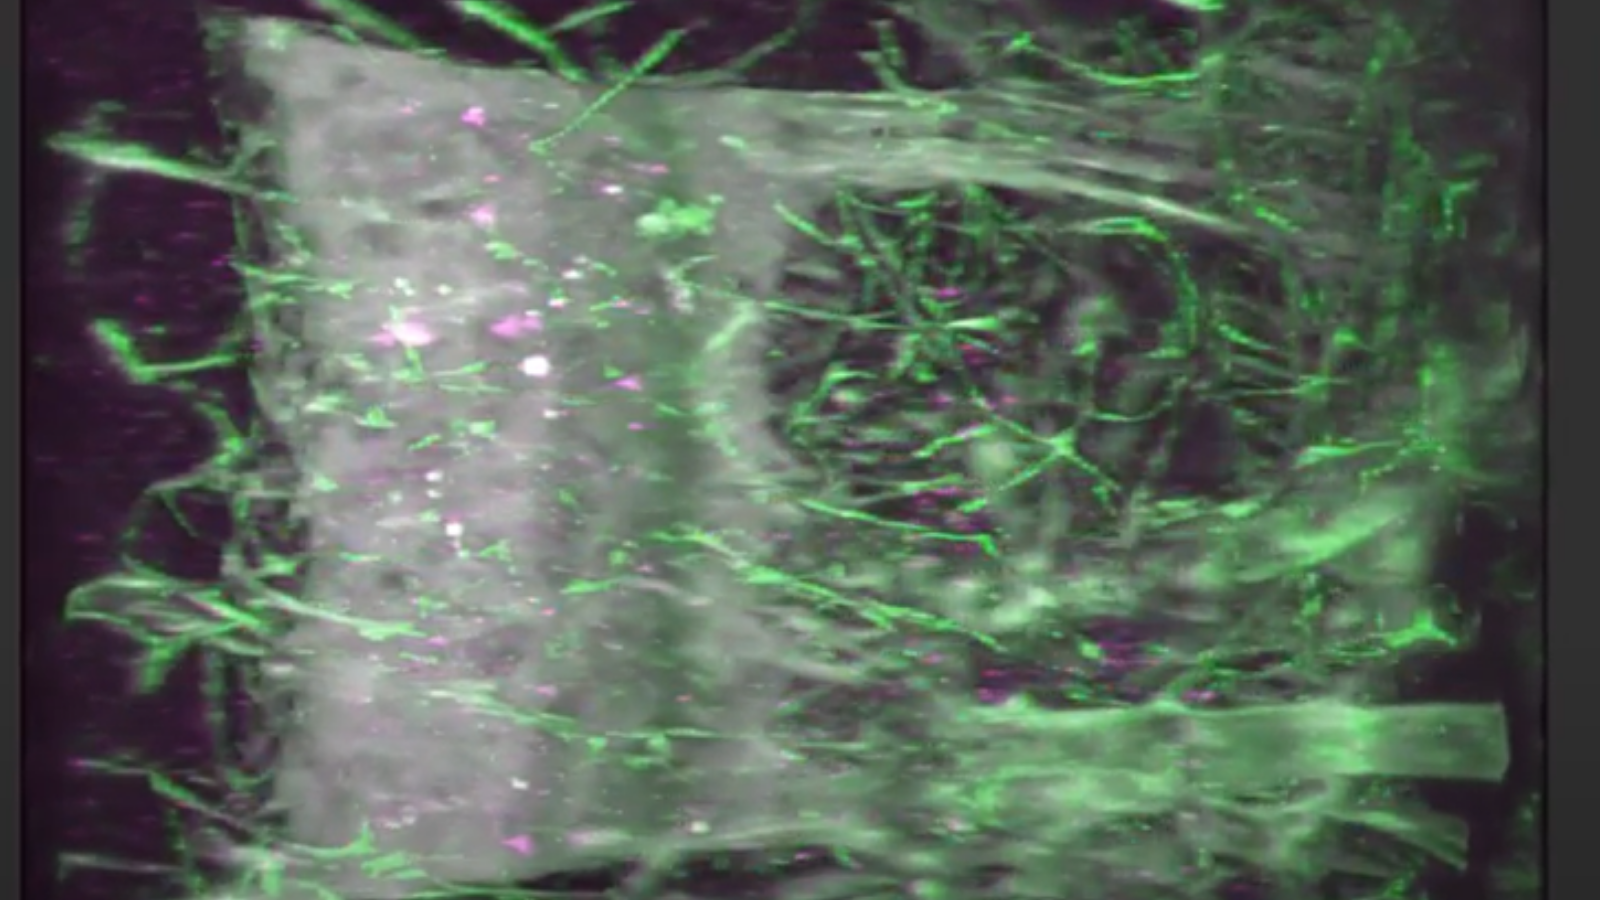

lightsheet image from University of Florida's, Seth Currlin, showing the neural network (green) within a human thymus, where the cells that fight infection mature.